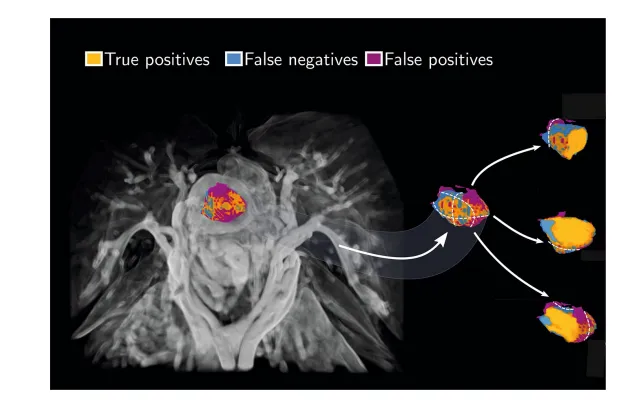

1. Figure 1:3D肿瘤分割可视化对比

左侧:AI分割与人工分割的3D体积渲染,橙色为真阳性(一致区域),蓝色为假阴性、紫色为假阳性(差异区域); -

右侧:3组轴位MRI切片+肿瘤局部放大,清晰展示AI与人工分割轮廓; -

关键发现:AI分割误差主要集中在肿瘤边缘,核心肿瘤区域识别高度精准。